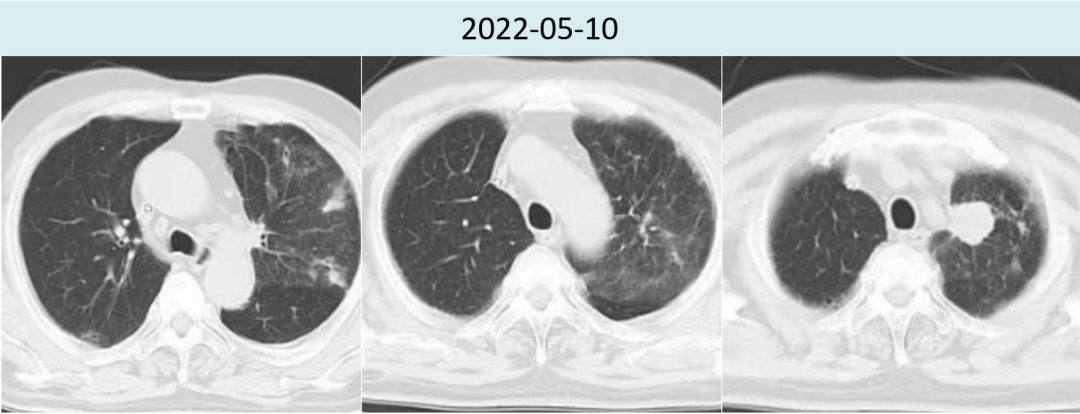

2022年5月10日胸部CT疗评进展(2.2cm→2.9cm)后,建议患者改三线化疗,患者拒绝。

2022年7月14日斯鲁利单抗联合安罗替尼治疗两周期后,胸部CT提示肿瘤病灶较前再次缩小,疗效评价PR(2.9cm→1.6cm),且两肺间质性炎症较前好转。

2022年10月17日斯鲁利单抗联合安罗替尼治疗六周期后,胸部CT提示肿瘤病灶较前继续缩小,疗效评价持续PR(2.9cm→1.4cm)。

图3.患者治疗前后胸部病灶及肺炎情况对比